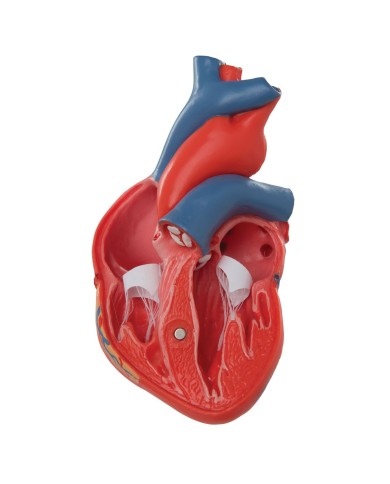

Fra i modelli di base segnaliamo il modello di cuore classico in due parti, in cui le due metà del cuore sono tenute insieme da potenti magneti.